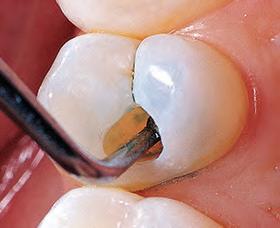

Sable Seek caries indicator contains FD&C dyes, and Seek caries indicator contains D&C dyes in a glycol base. Both are used to stain carious and demineralized dentin.

Seek and Sable Seek caries indicators stain carious and demineralized dentin and can be very useful for difficult-to-see areas, for example; undercuts of preparations, dark dentin, areas along the DE junction, etc. Green Sable Seek caries indicator helps visualization of decay in deep caries cases to help avoid pulp exposures.

PROCEDURE

dentin) with slow-speed round bur or excavator. To control overexcavating near the pulp, remove final portion of caries with hand excavator.